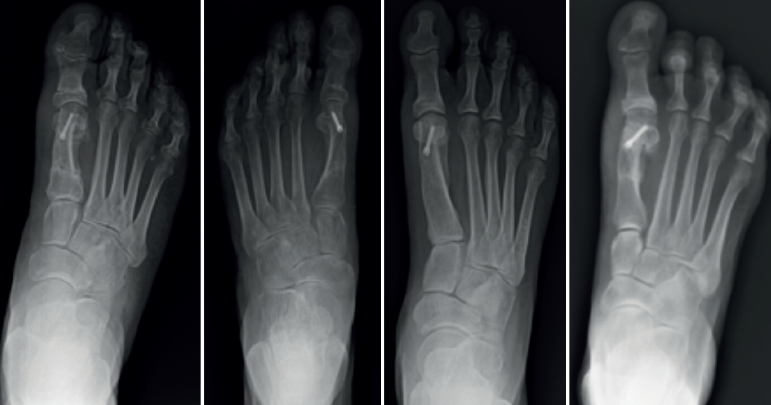

En 57 pacientes (75%) se utilizó una técnica de osteotomía diafisaria de tipo Scarf y en el resto una osteotomía distal de tipo Chevron, asociadas a osteotomía de Akin en la falange proximal en el 100% de los casos. El seguimiento presencial posquirúrgico en consulta fue de 3,3 meses de media (rango: 1-13; DE: 2,05), considerando el tiempo desde la cirugía hasta la última visita presencial en consultas en la que se considera que existe una restitución funcional completa, no agendando visitas presenciales posteriores, pero manteniéndose la posibilidad de una visita a demanda del paciente si apareciesen contratiempos durante el primer año tras la intervención.

En los 11 casos de hipocorrección de la deformidad, el AHV posterior a la cirugía fue de 18,86° de media (DE: 2,16), partiendo de un AHV considerado severo (> 40) en 8 de los casos y moderado (20-40) en 3 de ellos (Figura 1). En el caso de las hipercorrecciones observadas, la media de AHV tras la cirugía fue de −2,6° (DE: −3,25) (Figura 2). Tanto los casos descritos de hipocorrección como los de hipercorrección no tuvieron repercusión clínica en los pacientes en los que se presentaron, por lo que no fueron necesarios mayores actos terapéuticos posteriores.